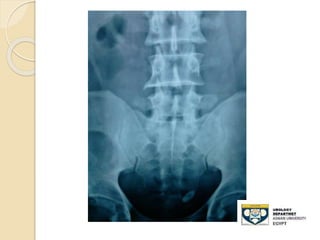

KUB film

 - Advantages:

◦ 80-90% of stones are radio-opaque

◦ Minimal radiation

 Disadvantages:

◦ Radiolucent stone

◦ Easy to miss mid-ureteral stones over the

sacrum

◦ Bowel gas can obscure its efficacy

◦ Cannot differentiate , Stones,Calcified LN

,

◦ Sensitivity: 50-70%

STONE UPPER THIRD URETER